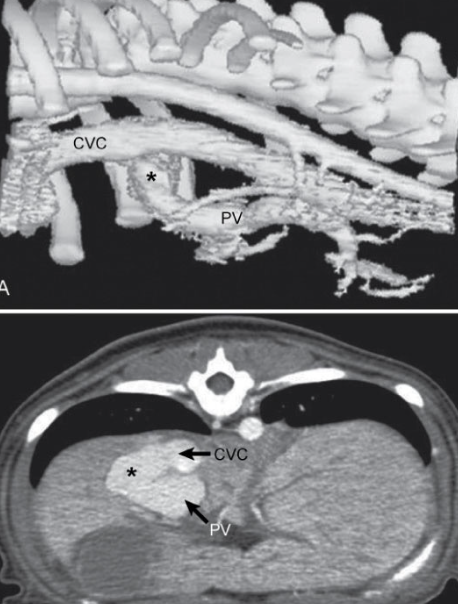

What imaging is available for PSS?

- CT angiography (gold standard for humans (and at OSU), non-invasive, fast, imaging of all portal tributaries)

- Portovenography

When is portovenography performed? What veins are used?

- Intraoperatively

- Jejunal or splenic vein

What does portovenography indicate?

- Where shunt diverges from portal vein

- Extrahepatic - Caudal to 13th thoracic vertebrae

- Intrahepatic - Cranial to 13th thoracic vertebrae